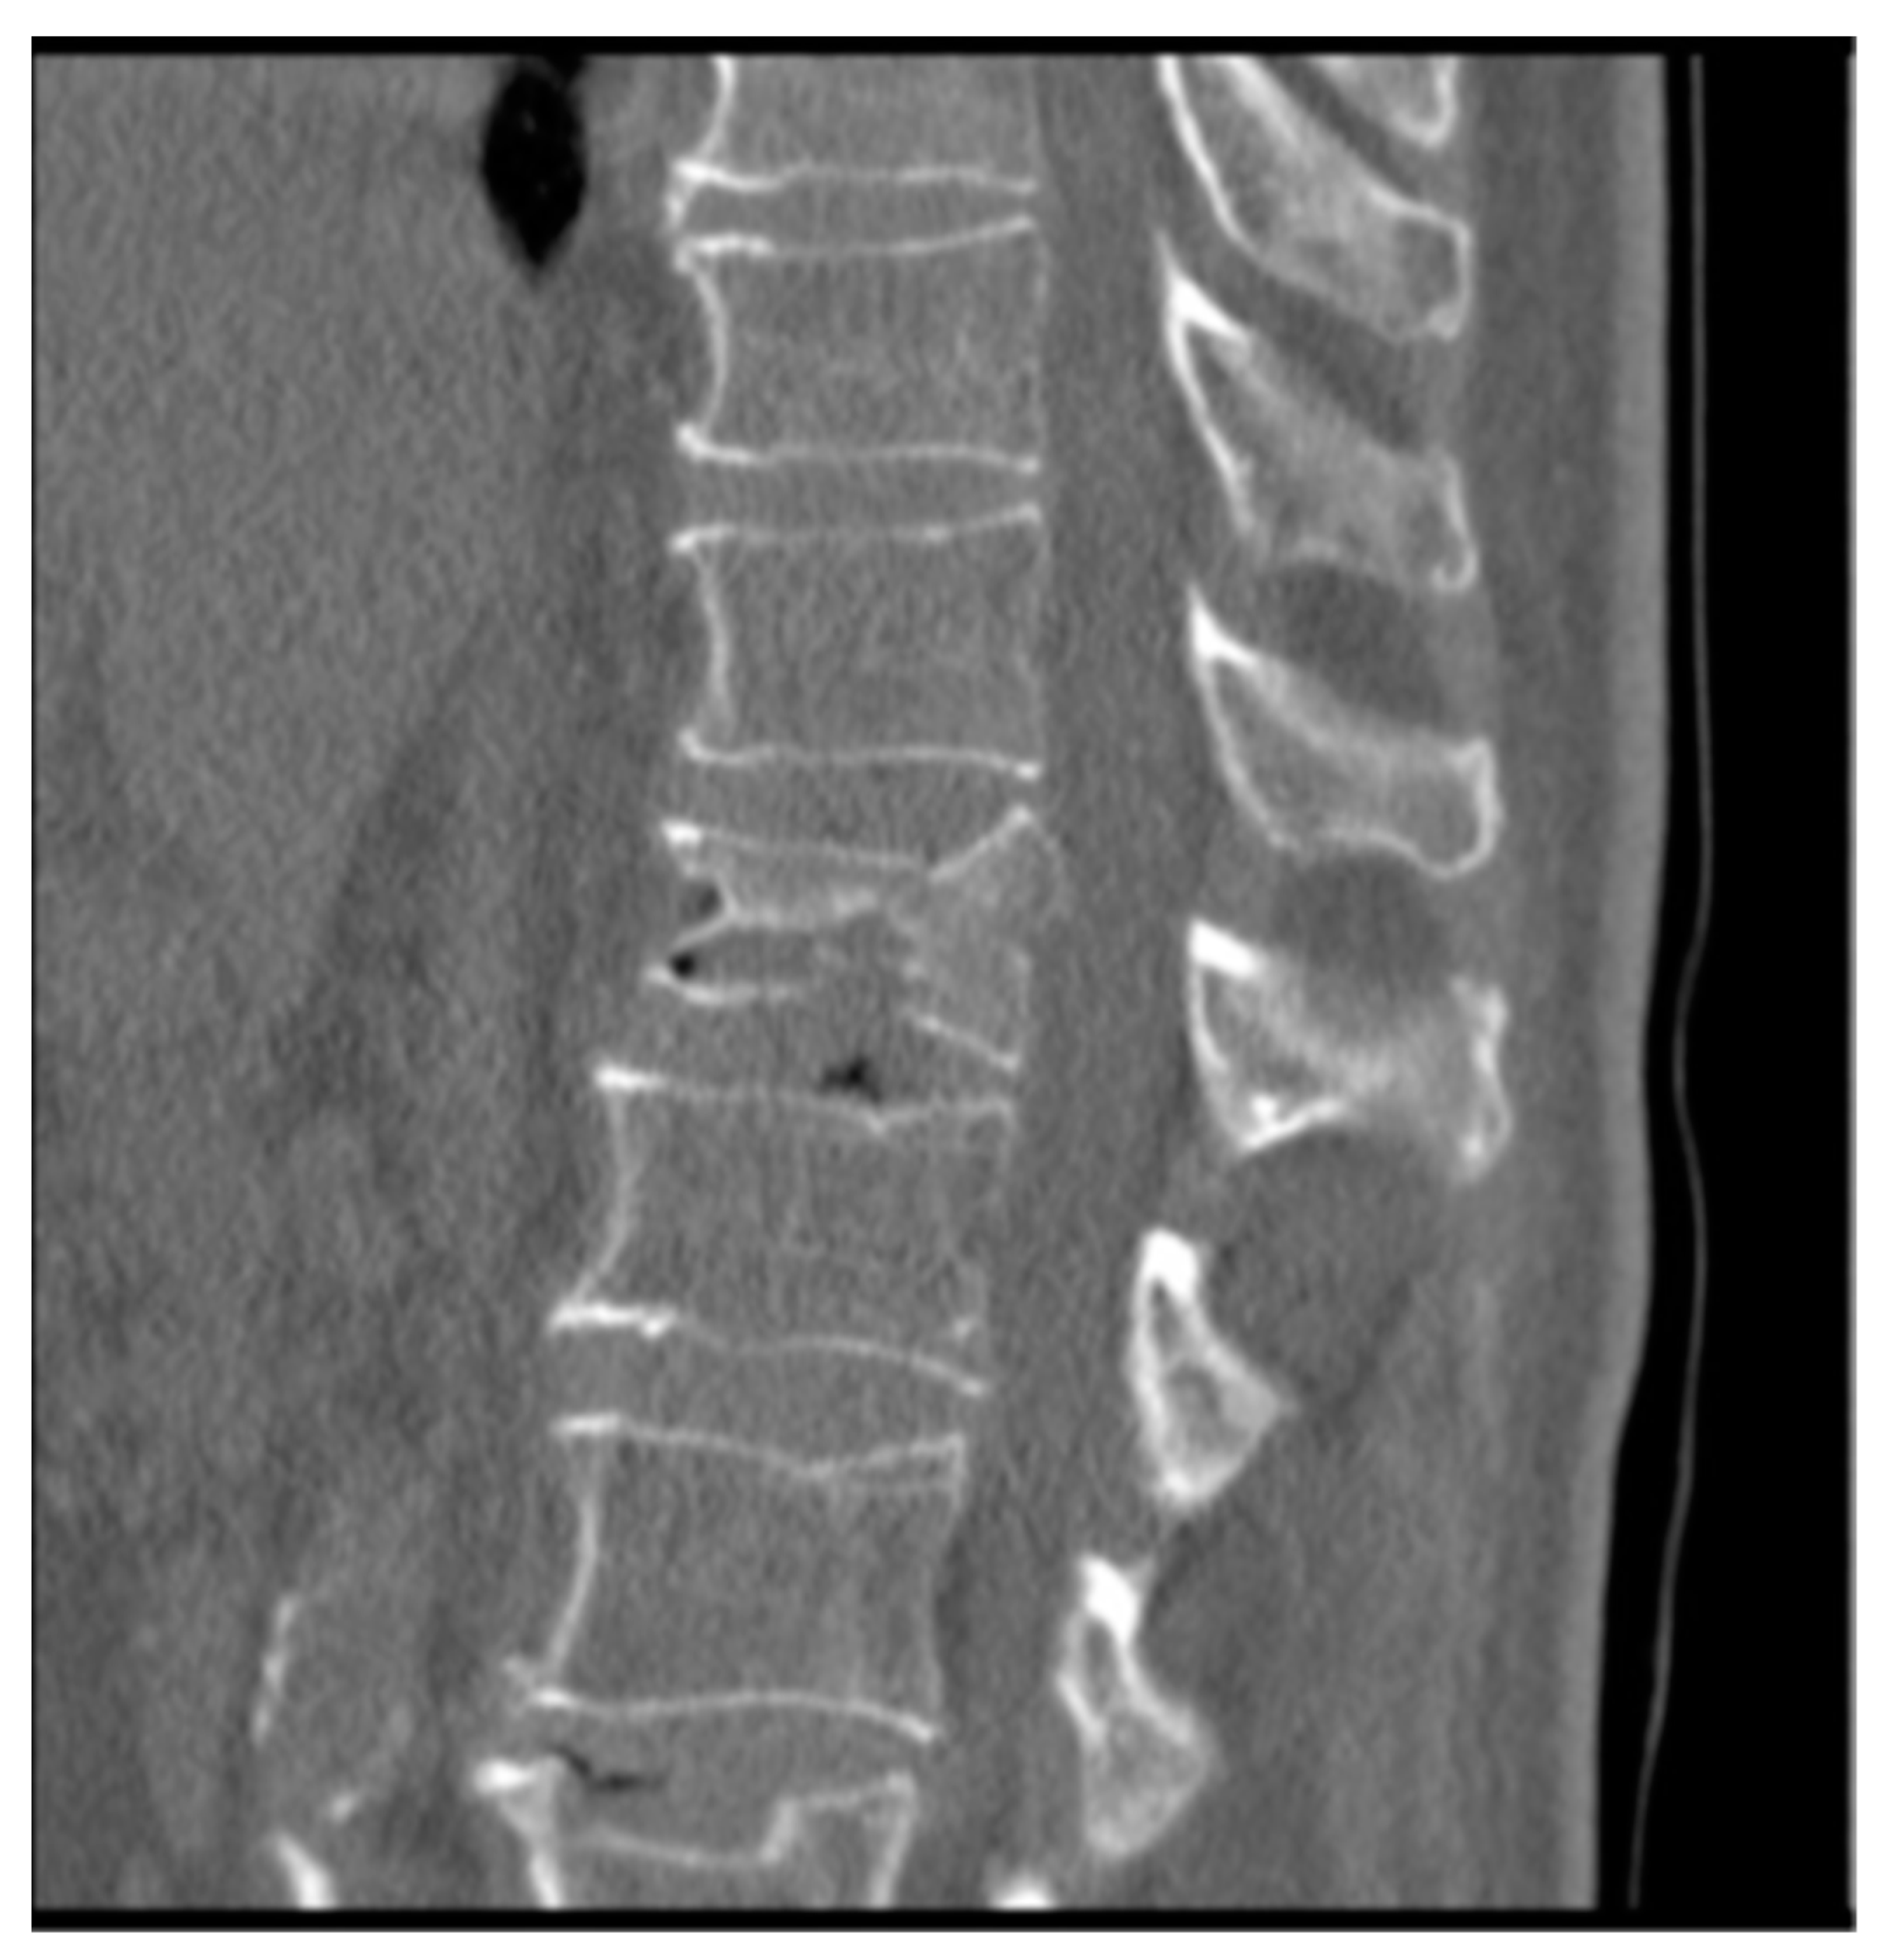

Male, 71-year-old, retired, affected by an osteoporotic bony condition. He experienced pain (9.1 on VAS scale) after a biconcave fracture in L1 (Figure 5). The imaging assessments showed that the two endplates have been affected by the fracture.

Figure 5.

CT with both end plates impacted of the L1 vertebra.